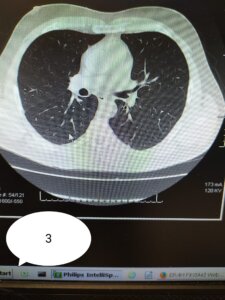

Galmozzi ha poi pubblicato 3 immagini di TC:

1) soggetto di 52 anni NON VACCINATO, senza malattie in anamnesi

2) soggetto di 70 anni NON VACCINATO, senza malattia in anamnesi

3) soggetto di 54 anni FRAGILE per severe copatologie VACCINATO

“Se in 1) e 2) il carico di malattia polmonare è elevato in 1 (circa 60%) e discreto in 2) (circa 35%). Nel soggetto 3) (fragile e con malattie importanti in anamnesi), la malattia non c’è. I primi due ricoverati e con ossigeno, il terzo a casa sua”.